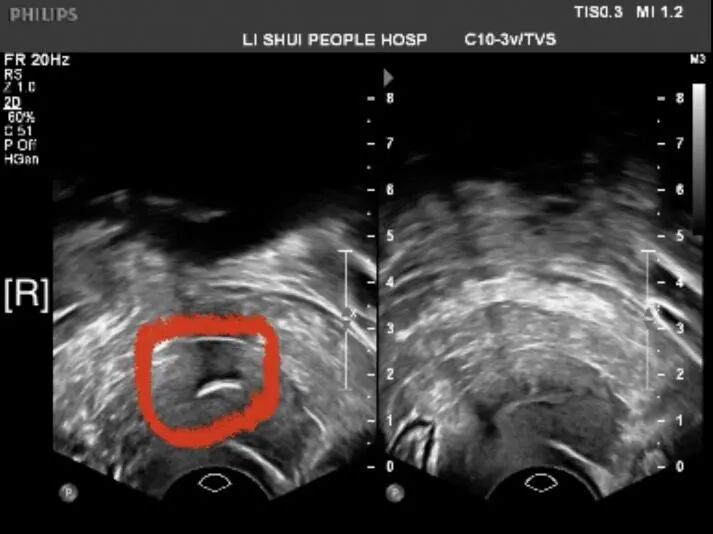

患者王女士(化名),今年60岁,已经绝经十年,她11年前取出放置在宫腔内的节育环,当时检查未见明显异常,近期,王女士自觉有下腹部不适感,前来门诊就诊,B超检查后却发现宫腔内有强回声存在,考虑为残留的部分节育环,同时,B超也提示在左侧附件区发现一枚囊性肿物。王女士要求住院进行手术取出残留在宫内的部分节育环,并切除附件肿物。 妇科主任邵莉萍带领妇科团队仔细询问病人病史并进行查体,发现患者已经绝经十年,由于绝经后女性卵巢功能衰竭,雌激素水平低落,宫颈及子宫明显萎缩,宫颈坚硬、宫颈管狭窄,进行宫腔操作前应进行充分的宫颈预处理,以便于手术操作,并降低手术风险,这也是绝经后女性宫腔操作成功的基础。如果宫颈扩张不充分,可能引发宫颈裂伤、子宫穿孔,甚至周围脏器损伤等严重并发症。因此宫腔操作前的宫颈准备十分重要。 宫颈除上皮成分外,主要由纤维结缔组织及少量平滑肌组成,结缔组织只有1%的弹性纤维,而胶原纤维含量占宫颈实质的70%左右,故组织伸展性较差,非妊娠状态下宫颈内口处于关闭状态。在宫腔操作前应通过使用药物和/或机械方法,使宫颈纤维结缔组织弹性增加,易于扩张,使宫腔操作更易进行,减少损伤。 故邵主任决定先给予宫颈预处理,结合雌激素应用增加宫颈组织的弹性,再逐步扩张宫颈以达到可以进行宫腔镜手术操作的标准,并在术前放置宫颈扩张条。同时,患者检查发现左侧附件肿物,结合超声及腹部CT检查考虑为输卵管积水可能,输卵管积水大多都是由于输卵管炎症引起的,需要及时进行治疗,否则长期的炎症刺激会引发病变,甚至癌变。所以,经过慎重考虑,邵主任决定给予患者宫腹腔镜联合手术,同时解决两个问题。王女士和家属了解病情后同意了手术方案。 经过充分的宫颈预处理后,6月8日,邵莉萍主任带领妇科医师团队给王女士在全身麻醉下进行了宫腹腔镜联合手术。腹腔镜下可以清楚地看到左侧输卵管呈腊肠状扭曲增粗,符合输卵管积水的改变,切除左侧输卵管后再进行宫腔镜下手术。 然而,由于患者绝经时间久,宫腔内粘连致密,宫腔镜逐步进入后见假道形成,假道有着类似宫腔的腔体,但四壁均为肌肉纤维,不符合宫腔内正常形态。 任何原因都可能导致假道的产生,如紧致的宫颈、宫颈管狭窄、偏离的宫颈管通道或子宫急性的角度扭曲(子宫极度前倾或后屈)。假道会增加膨宫介质的吸收,尤其是在子宫肌层内形成的假道,会打开更大的血管通道。这可能导致体液稀释和严重的并发症,如果未识别假道,继续置入镜体可能导致子宫穿孔以及与其相关的所有并发症,例如肠道损伤或大量出血。识别假道后,动作应非常轻柔缓慢地撤出宫腔镜,以便识别宫颈管的外口,评估假道并寻找真正的宫腔。 邵主任立即将宫腔镜后退,在宫颈管内重新寻找宫腔开口,假道的存在对探查真正的宫腔带来极大的干扰,在进一步分离粘连后终于发现真正的宫腔开口,并在宫腔内发现了残留的部分节育环,长约1cm,完整取出残留的部分节育环,再次检查宫腔内未见异常组织。手术顺利结束。 科技是为人服务的,每一项技术都能给患者带来更好的治疗。我院妇科团队长期开展宫腹腔镜联合手术、宫腔镜子宫内病损切除、宫腔镜子宫内异物取出等先进技术,旨在提高我们的服务质量,更好地为广大女性服务。 |